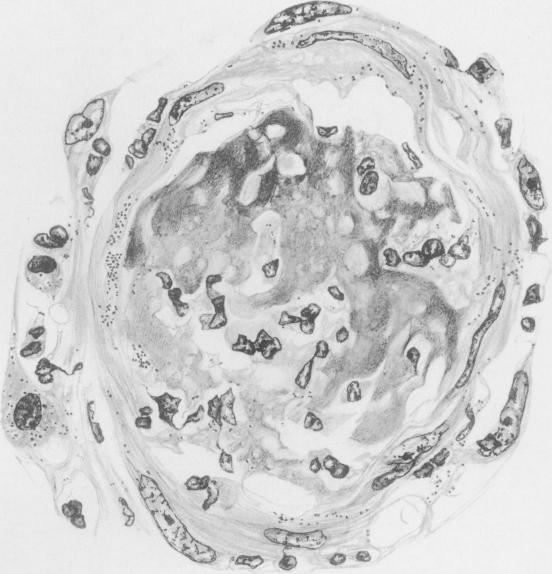

Studies on Rocky Mountain spotted Fever.

J Med Res. 1919 Nov;41(1):1-198.41.